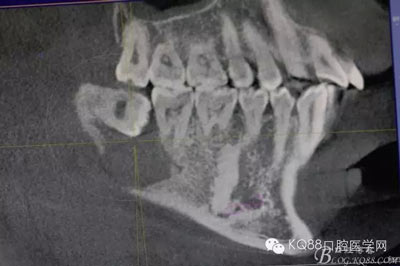

圖9.不斷的耐心去骨,發(fā)現(xiàn)48被下方的囊性改變趕到舌側(cè)。

圖10 開始分牙,術(shù)中分牙經(jīng)歷非??部?,鉆頭操作異常困難,因?yàn)?8倍囊性改變推至舌側(cè)。

術(shù)前認(rèn)為48埋伏阻生,導(dǎo)致下方囊性變發(fā)生,術(shù)中感覺,48埋伏似乎與下方囊腫沒有直接關(guān)聯(lián),如果是其導(dǎo)致的囊性改變,48拔除難度不大,實(shí)際上48被囊性改變推至舌側(cè),導(dǎo)致48拔除難度增大。術(shù)前的檢查只能提供參考,還需要術(shù)者在術(shù)中認(rèn)真操作,仔細(xì)分析才行。